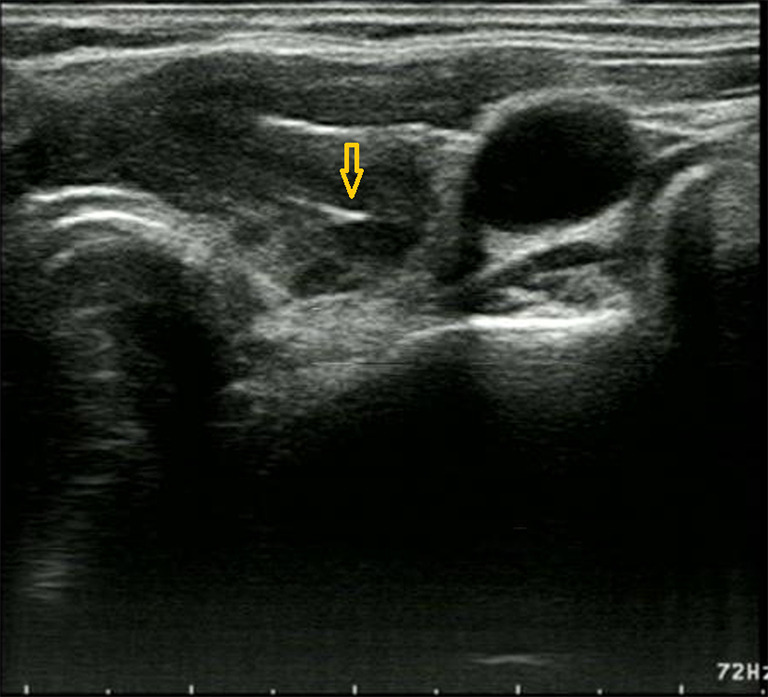

Case description: A 68-year-old woman visited Baoji Central Hospital following ultrasound (US) performed at another hospital indicated a suspicious malignant nodule in her thyroid. Physical examination and thyroid US revealed a hard mass and irregular hypoechoic area in the right lobe, suggesting a possible malignant lesion. Ultrasound-guided FNAC (US-FNAC) was suspicious for PTC. The patient subsequently underwent right thyroid lobectomy and isthmusectomy, and postoperative histopathology revealed an epithelioid granulomatous lesion without tumor tissue. Meanwhile, postoperative serum testing revealed elevated TB-γ interferon concentration, and a specific T lymphocyte testing was positive, indicating a tuberculosis infection. Primary thyroid tuberculosis was ultimately confirmed. Postoperatively, the patient recovered well after surgery and received anti-tuberculosis therapy in a tuberculosis hospital for 1 year.